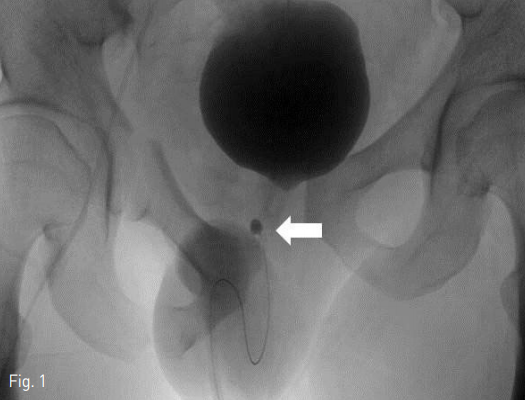

전산화단층촬영에서 복합골반골절과 이와 동반된 속장골동맥에서의 조영제 유출 소견과 함께 많은 양의 골반내외 혈종이 확인됨. 방광은 이 혈종에 의해 눌려 있는 양상으로 전립선 아래 부분 부위부터의 요도는 파열되어 있었고, 파열된 요도간의 거리가 멀어져 시술 직전 응급소생구역에서 삽입된 요도관의 풍선은 골반의 자유공간에서 부풀려져 있음. 색전술이 끝나고 시행한 fluoroscopy상에서 조영제가 차 있는 방광과 이와 거리를 두고 아래쪽 골반 강에서 거치된 요도관의 풍선이 보여 전산화단층촬영에서 확인된 복합골반골절에 동반한 후부요도파열에 합당한 소견임 (Fig. 1).

Fig 1

Fluoroscopy in a 32-year-old man shows complex pelvic fracture with contrast filling of the urinary bladder. The end (arrow) of the Foley catheter is not in the bladder.